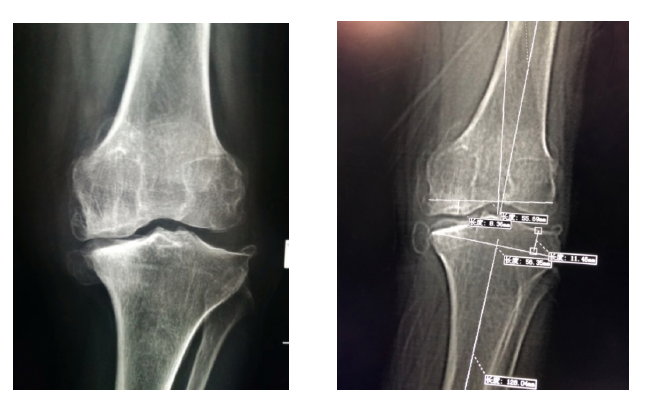

術前手術規劃

術中精準操作